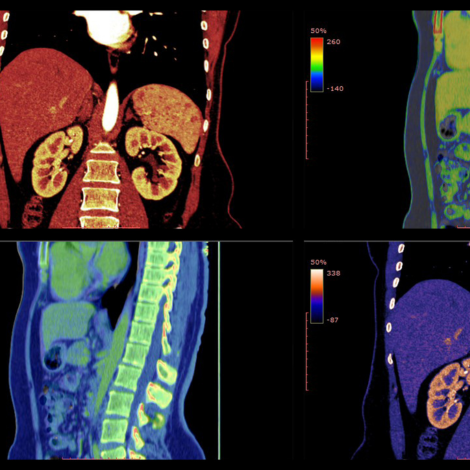

KUB CT

CT scan KUB means Computed Tomography of the Kidneys, Ureters, and Bladder. The scan is helpful in getting images of the urinary system. Common indications include renal stone disease, diagnose and assess infection / tumors of the urinary tract and other causes of abdominal pain.

Abdomen & Pelvis CT

The abdomen and pelvis contains organs of the gastrointestinal, urinary, endocrine, and reproductive systems. A CT scan of the abdomen may be performed to assess the abdomen and its organs for tumors and other lesions, injuries, intra-abdominal bleeding, infections, unexplained abdominal pain, obstructions, or other conditions, particularly when another type of examination, such as X-ray, ultrasound or physical examination, is not conclusive. A CT scan of the abdomen may also be used to evaluate the effects of treatment on abdominal tumors. Another use of abdominal CT is to provide guidance for biopsies and aspiration or either of the tissue from the abdomen.